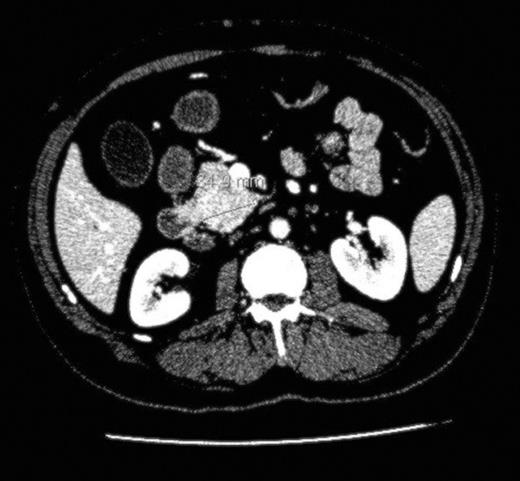

We report the case of a 61 year old man, previously treated for follicular lymphoma in the left groin with radiotherapy, presentING to our hepatobiliary department with painless obstructive jaundice ALP 592 iu/L (40-130), ALT 86 iu/L (2-53) and Bil 180 (3-17). His CA19.9 was 156 u/l and there was no clinical evidence of tuberous sclerosis. Cross-sectional imaging in the form of a CT and MRI scan reported multiple suspicious lesions in the liver (Fig. 1) and a small lesion in the uncinate process of the pancreas (Fig. 2) causing intrahepatic and common bile duct dilatation. The radiological diagnosis at this point was of a metastatic (and hence inoperable) pancreatic cancer. He underwent an ERCP and insertion of a CBD stent to relieve his jaundice and an attempted percutaneous biopsy of his pancreatic mass yielded inadequate cells. He then underwent a laparoscopy and attempted biopsy of his pancreatic and/or liver lesions. The pancreatic mass was difficult to visualise on intraoperative ultrasound however one of the liver lesions was biopsied and this was reported as an angiomyolipoma.

After re-discussion at our multi-disciplinary meeting it was felt that on balance the liver lesions were an incidental finding and in view of his age, presentation and imaging he most likely had a small pancreatic carcinoma. He underwent a pancreaticoduodenectomy and made an uneventful recovery. Histological analysis of the specimen revealed a small completely excised angiomyolipoma. Several months after his operation, he was admitted with vague abdominal pain, which resolved spontaneously. However, a CT scan performed during his admission revealed several intra-hepatic lesions of varying sizes and a growth of the original segment VI lesion. A percutaneous biopsy of one of the new lesions once again confirmed AML.